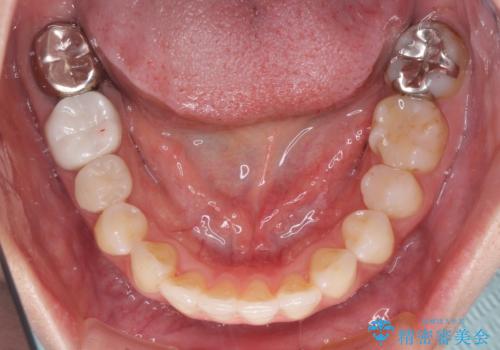

総合歯科治療 矯正治療と失活歯のセラミック補綴治療

- 失活により変色した歯と不揃いな口元を気にして来院された患者様です。

口元をインビザラインにより歯列を整え、その後に失活している奥歯をオールセラミッククラウンにて補綴治療することとしました。

長時間のマウスピース装着と、患者様自身でのゴムかけに協力いただき、自然な口元に仕上げることができました。

気になっていた変色した歯もオールセラミッククラウンで本物の歯のようになり、患者様には大変満足していただきました。